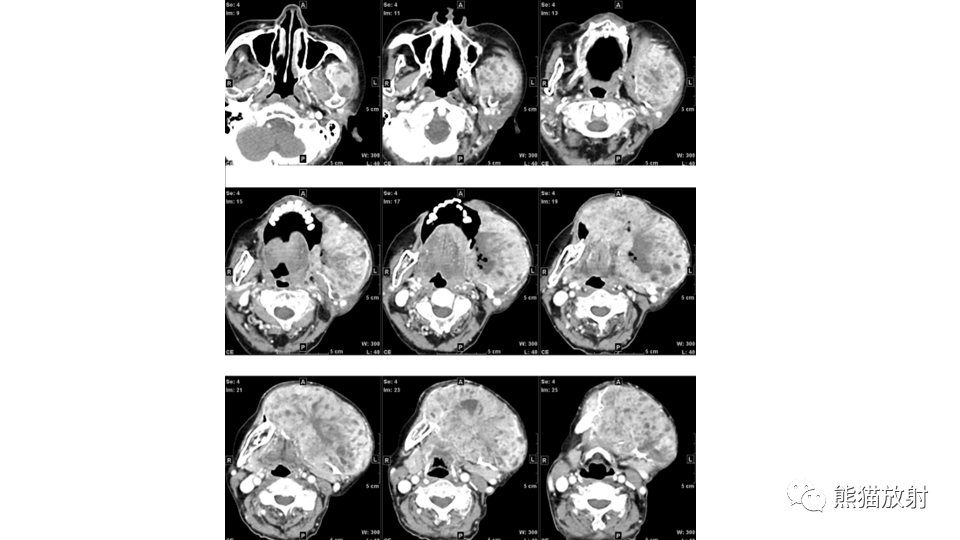

【病例】下颌骨成釉细胞瘤2例CT-3

【病例】下颌骨成釉细胞瘤2例CT-4